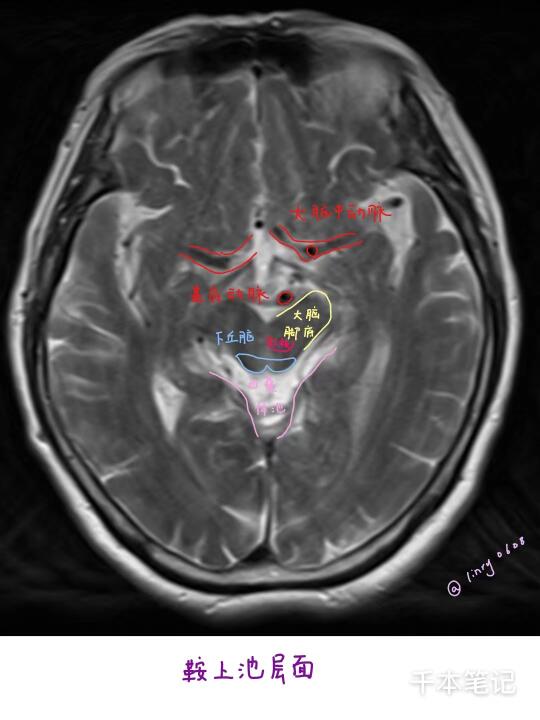

在黑白灰的世界里,加上了现在热爱的多巴胺色系笔触,显然没有什么是比鲜活的生命更动人的事情了,还是一遍遍的在学习和革新着自己,不加标签,接受好的与坏的评判,以及一个不完美的自己。